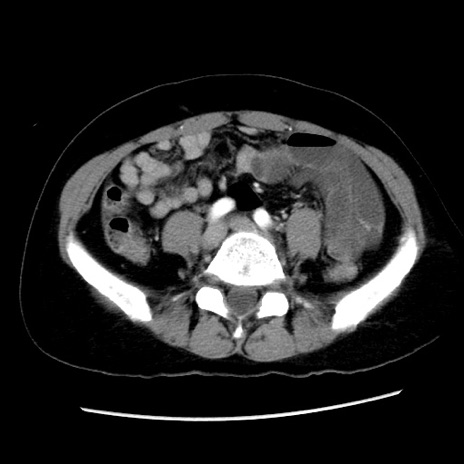

症例10(横断像)

【症例】 50歳代女性

【主訴】 腹痛

【現病歴】前日生レバーを食べた。今朝に排便あり。 昼前に突然発症の腹痛を生じ、当院救急外来を受診した。

【既往歴】 子宮筋腫にてで子宮全摘後

【身体所見】 意識清明、腹部:平坦、軟、下腹部やや左を中心に圧痛・反跳痛あり、筋性防御あり

【データ】WBC 7800、CRP 0.07